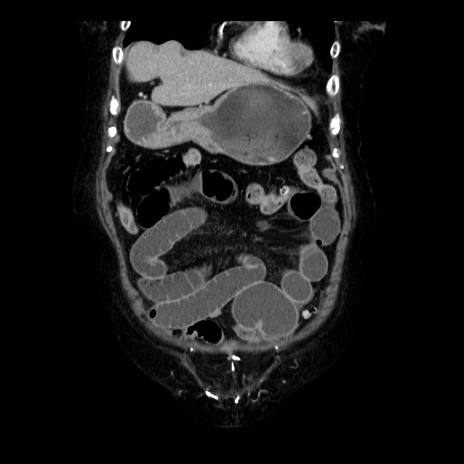

症例14(冠状断像)

【症例】 90歳代女性

【主訴】 腹痛・嘔吐

【現病歴】今朝から左側腹部痛を認めた。 経過観察していたが、嘔吐を認めたため来院。

【既往歴】 子宮癌術後

【身体所見】 意識清明、BP 127/54mmHg、P 98bpm Sp02 95%(RA)、BT 35.8°C、腹部平坦・軟腸ぜん動音聴取良好、右下腹部圧痛(+) 反跳痛なし

【データ】WBC 9800、CRP 0.46